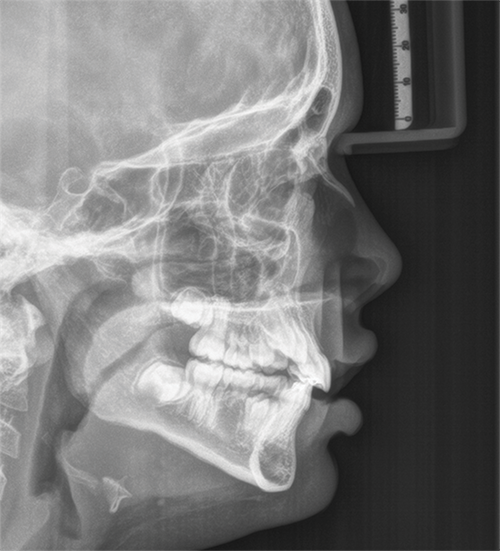

When a 9-year-old patient presents missing all four second premolars (5s) and second molars (7s), the treatment planning can be tricky. The discussion on the message boards raised the question of timing extractions and how to encourage natural drift without compromising the facial profile (Fig. 1).

Fig. 1